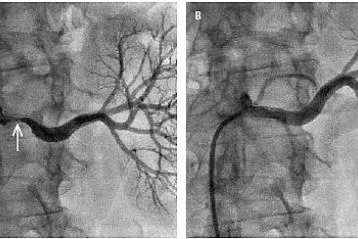

Wiele osób sądzi, że podwyższony cholesterol to nic takiego, w końcu wiele osób taki ma. Wszystkie te osoby pragnę uświadomić, że taka sytuacja stopniowo doprowadza do upośledzonej przepustowości naczyń, a w konsekwencji do poważnych kłopotów zdrowotnych. Do tego dochodzą często bóle klatki piersiowej, szybka męczliwość po znikomym wysiłku, drętwienie rąk i nóg, pieczenie, obrzęki, zasinienie i „marmurkowa” skóra, a w najgorszych przypadkach nawet niewydolność narządów lub procesy martwicze. Wysoki cholesterol wymaga natychmiastowej reakcji.

Prowadzone badania wykazały, że działanie składników zawartych w formule Cariovico niemal natychmiast obniża „zły cholesterol”, czyli jego frakcję LDL, jednocześnie normalizując gospodarkę glukozowo-lipidową organizmu. Dzięki temu Cariovico minimalizuje odkładanie się blaszek miażdżycowych w tętnicach.

Przywrócenie prawidłowego profilu cukrowo-tłuszczowego organizmu jest niezwykle istotne, ale to nie wszystko. Cariovico posiada zdolność rozmiękczania, rozluźniania i – ostatecznie – stopniowego rozpuszczania nagromadzonych latami groźnych złogów w naczyniach krwionośnych. Są one w bezpieczny sposób wypłukiwane z organizmu.

Cariovico działa wielopłaszczyznowo. Nie tylko przywraca ciału jego właściwą biochemiczną równowagę i działa udrażniająco na zblokowane lipidami naczynia tętnicze. Ponadto uelastycznia i wzmacnia delikatne tkanki naczyń krwionośnych, poprawiając ich kondycję i zapobiegając obrzękom.

Za sprawą starannie wyselekcjonowanych, maksymalnie stężonych składników, ścianki naczyń krwionośnych zostają oczyszczone ze złogów nawet w 91%, a tlen i substancje odżywcze mogą swobodnie płynąć do tkanek. Prawidłowe krążenie krwi i właściwa praca układu naczyniowo-sercowego to klucz do długiego, zdrowego życia i świetnej kondycji.